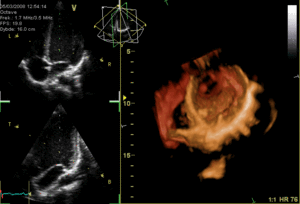

Imaging

Several imaging methods can be used to assess the anatomy and function of the heart, including ultrasound (echocardiography), angiography, CT scans, MRI and PET. An echocardiogram is an ultrasound of the heart used to measure the heart's function, assess for valve disease, and look for any abnormalities. Echocardiography can be conducted by a probe on the chest ("transthoracic") or by a probe in the esophagus ("transoesophageal"). A typical echocardiography report will include information about the width of the valves noting any stenosis, whether there is any backflow of blood (regurgitation) and information about the blood volumes at the end of systole and diastole, including an ejection fraction, which describes how much blood is ejected from the left and right ventricles after systole. Ejection fraction can then be obtained by dividing the volume ejected by the heart (stroke volume) by the volume of the filled heart (end-diastolic volume).[78] Echocardiograms can also be conducted under circumstances when the body is more stressed, in order to examine for signs of lack of blood supply. This cardiac stress test involves either direct exercise, or where this is not possible, injection of a drug such as dobutamine.[72]